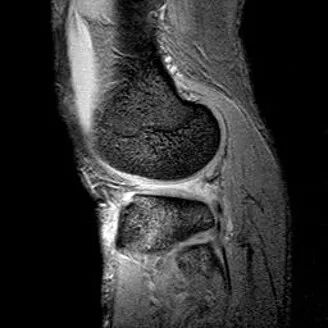

最常见类型:斜行撕裂表现为:在矢状面上见III级高信号到达半月板关节面的上缘或下缘

半月板斜行撕裂